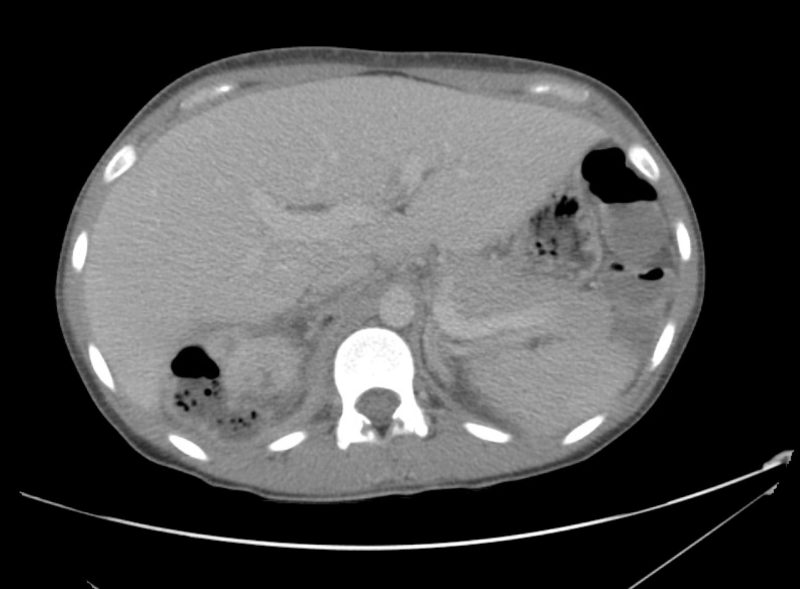

from ddxof.com

15_pyelo Differential Diagnosis of